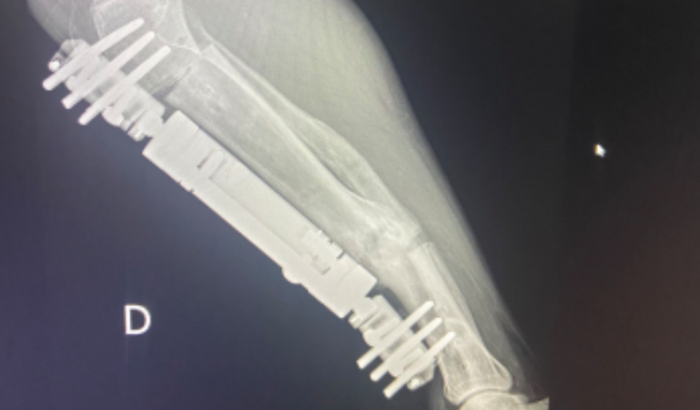

No dia 30/10/2014, eu fui atropelado às 7h30 da noite na avenida das Américas, no estado do Rio de Janeiro. De lá para cá, eu venho enfrentando muitas dificuldades. Já realizei diversos procedimentos cirúrgicos tanto no braço como no rosto, mas a maioria deles foi na perna. Onde eu me encontro com total de 25 cirurgias na perna e só no mês passado eu fiz duas cirurgias de transposição ósseo. Pelo excesso de anestesia de medicamento, meu organismo acabou criando alguns tipos de resistência. Vivo com muita dificuldade de locomoção e algumas dificuldades em questão de dor. Preciso desse medicamento, porém o medicamento é muito caro e eu não tenho como custeá-lo. Peço ajuda de vocês para poderem me ajudar a comprar o meu medicamento, pois ele é o único medicamento que tira minha dor. O dia em que eu não tomo ele, eu não consigo andar, mesmo que você não possa me ajudar, compartilhe, pois isso já estará me ajudando. Obrigado a todos!